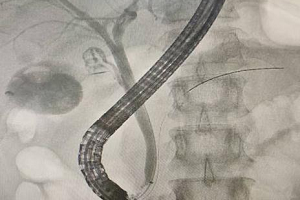

近日,玉溪市人民医院疼痛科团队成功开展首例4K无线内窥镜下UNSES/AUSS手术,为颈肩腰腿痛、椎间盘突出、椎管狭窄等患者提供更精准、更微创的治疗新选择。